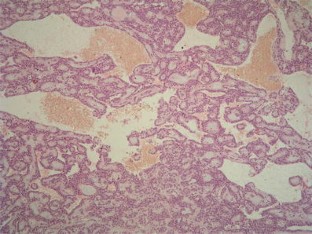

Fig. 1

Fig. 2

Fig. 3

Fig. 4

Fig. 5